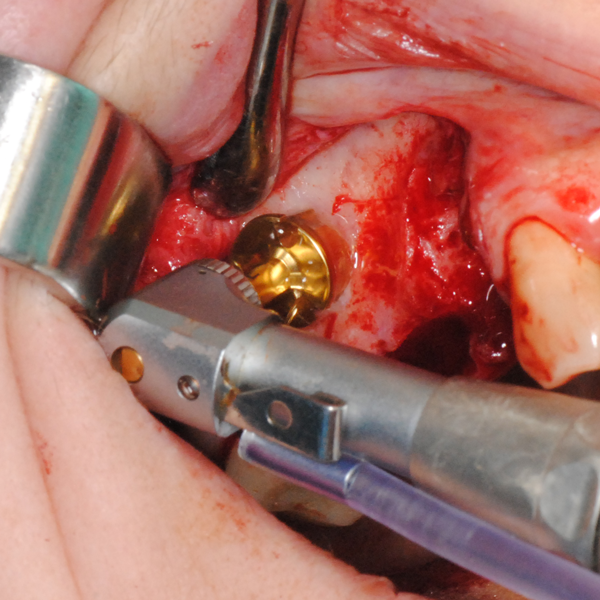

Видеоклип за открит синуслифтинг Пластинка Сasios

Отворен максиларен синус в началото на интервенцията. Случаят е интересен със следното - твърде атипична форма на трепанационния отвор. На какво се дължи на това - на лошо планиране на оперативния достъп или на нещо друго? Дължи се на факта, че отначало въпросната намеса беше планирана като балонен синуслифт; за съжаление обаче мембраната на синуса се разкъса и надуването на балона стана невъзможно.